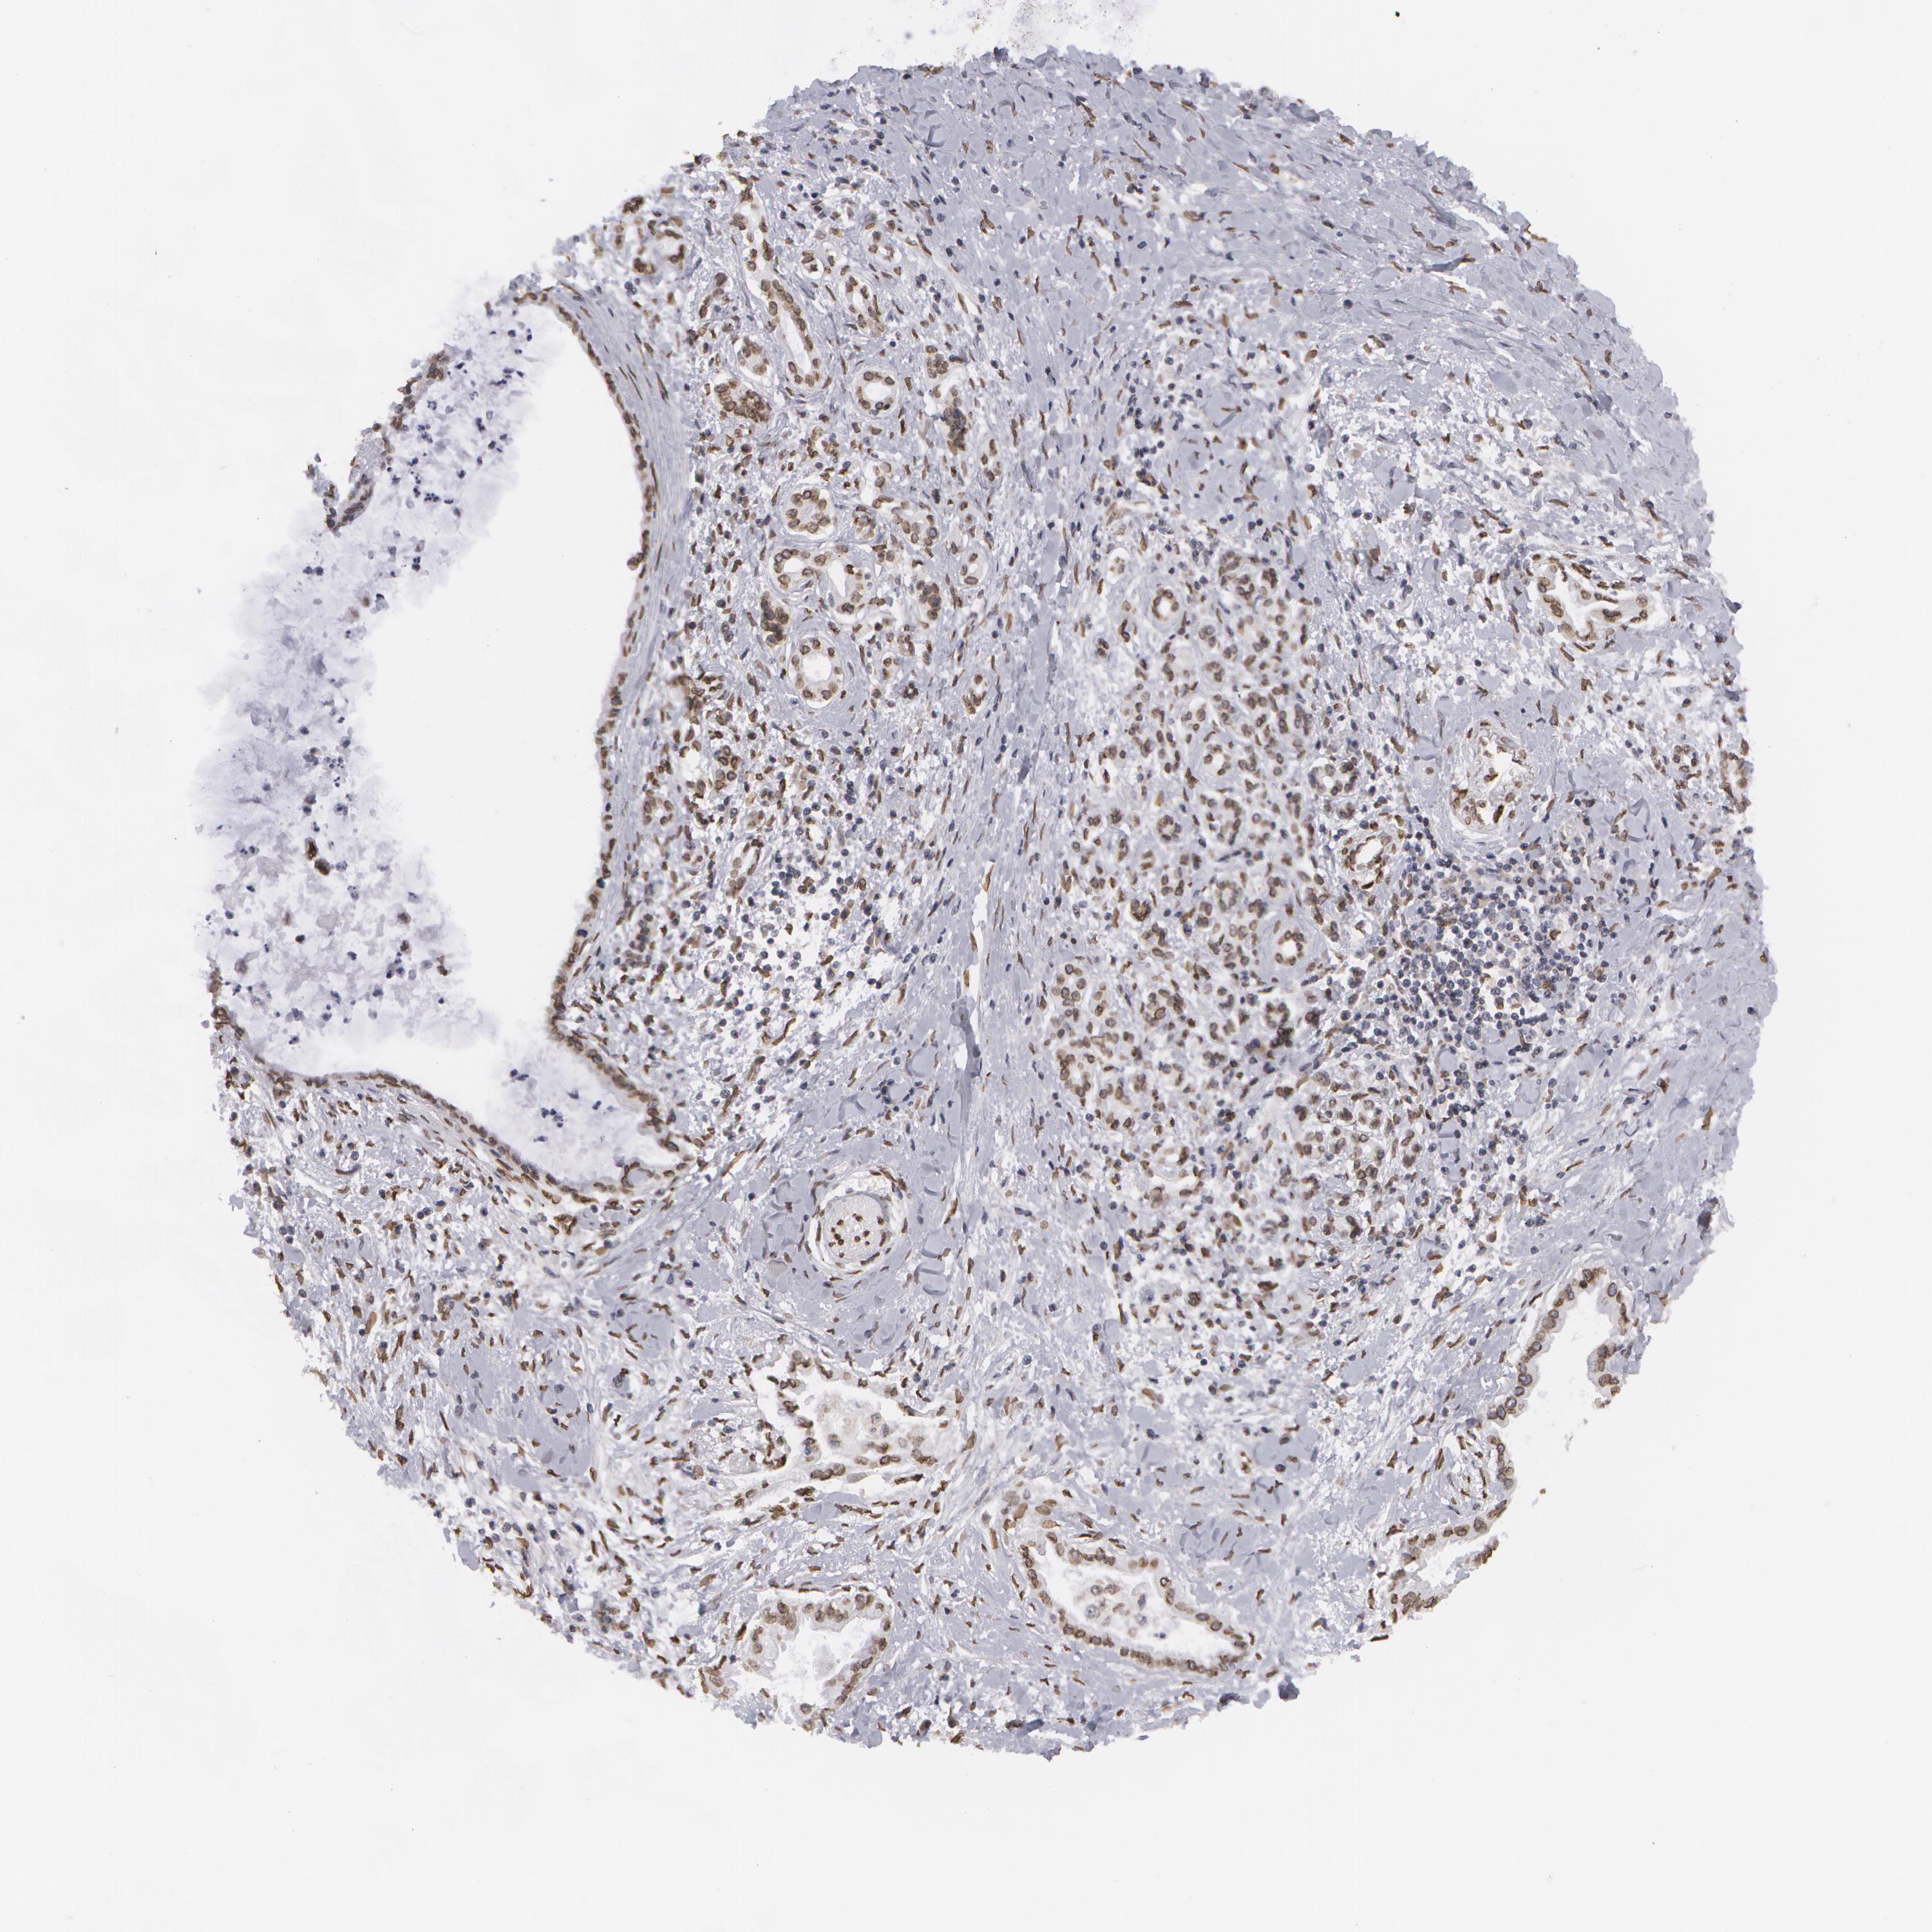

PANCREATIC CANCER - Protein expressioni

A mouse-over function shows sample information and annotation data. Click on an image to view it in a full screen mode. Samples can be filtered based on level of antibody staining by selecting one or several of the following categories: high, medium, low and not detected. The assay and annotation is described here.

Note that samples used for immunohistochemistry by the Human Protein Atlas do not correspond to samples in the TCGA dataset.

Antibody stainingi

Antibody staining in the annotated cell types in the current human tissue is reported as not detected, low, medium, or high, based on conventional immunohistochemistry profiling in selected tissues. This score is based on the combination of the staining intensity and fraction of stained cells.

Each image is clickable and will lead to virtual microscopy that enables deeper exploration of all samples and also displays staining intensity scores, fraction scores and subcellular localization as well as patient and tissue information for each sample.

Antibody HPA000609

Antibody CAB001545

Antibody CAB002029

Antibody CAB062552

Staining

High

Medium

Low

Not detected

Intensity

Strong

Moderate

Weak

Negative

Quantity

>75%

75%-25%

<25%

None

Location

Nuclear

Cytoplasmic/membranous

Cytoplasmic/membranous,nuclear

Adenocarcinoma, NOS